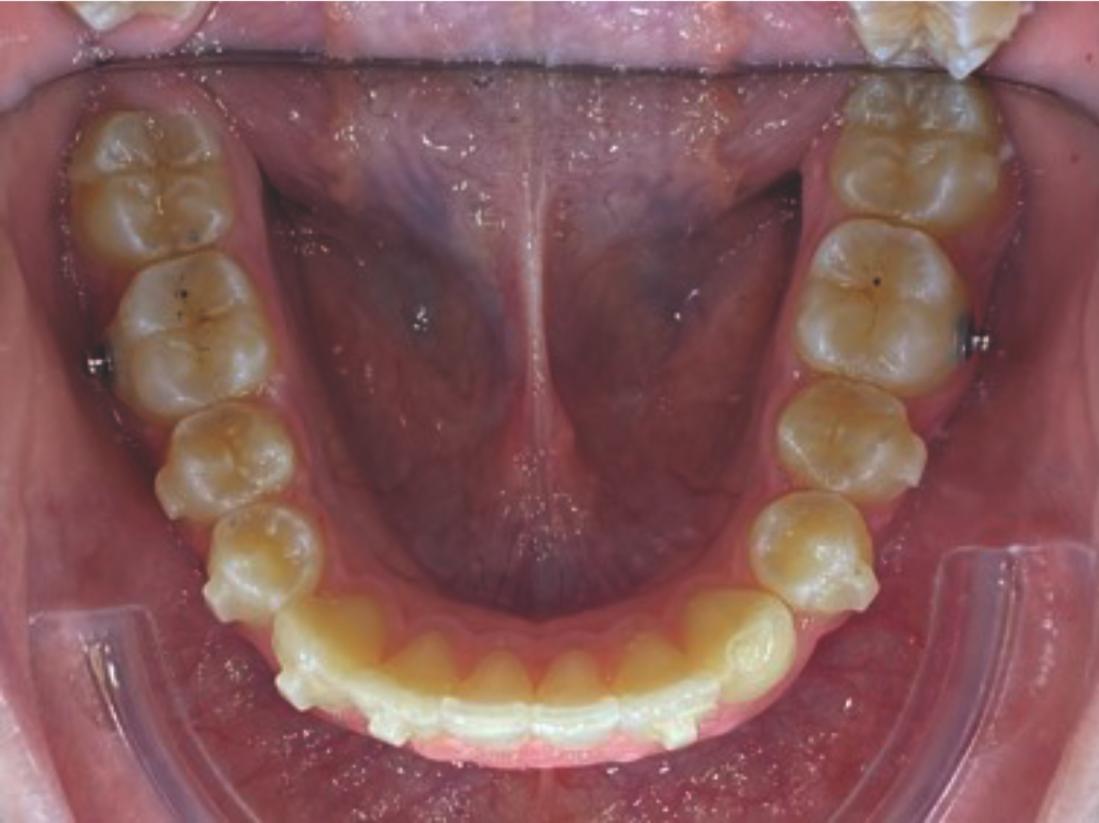

We approached the case by combining upper distalization using the A8 protocol with an asymmetric virtual jump. In this way, we solved the crowding without proinclining the incisors and improved the anteroposterior relationship through the use of elastics. In the lower arch, we carry out a development of the posterior sectors prior to the resolution of the crowding, in order to avoid roundtripping and excessive IPR of the incisors. To achieve an effective extrusion and distalization of 13, we combine the use of direct bonding button on vestibular of 13, with angelButton elastics mesial and distal to the canine. These mechanics help to ensure that the extrusion is real and that the aligner always remains adapted.

Treatment details

In the upper arch, the main goal will be to correct the Class II malocclusion by distalizing the upper posterior teeth in order to resolve crowding without proinclining the incisors. This movement will be accompanied by an asymmetric “bite jump” of 1 mm, which will help improve the skeletal Class II discrepancy, promoting mandibular projection, especially considering that the patient is still in the growth phase. Additionally, bilateral and symmetric expansion will be planned until a torque of 0° is achieved, allowing for proper transverse alignment and greater stability of the final result. Lingual button cutouts will be placed on teeth 14 and 24 to facilitate the required movements. To optimize control and retention, vertical mesial beveled attachments, as large as possible, will be placed on the premolars and molars, as well as on teeth 12 and 22, reinforcing the mechanics in the anterior sector. The inclination of the central incisors 11 and 21 will be corrected according to the visual reference provided in the clinical image. Furthermore, it will be necessary to center the upper midline by shifting it 0.5 mm to the left to achieve greater aesthetic symmetry. As for the lower arch, treatment will begin with a phase of expansion and derotation of the posterior teeth, which will set the stage for subsequent movements in the anterior sector. Once this goal is achieved, alignment of the teeth from canine to canine will proceed, aiming to minimize anterior interproximal reduction (IPR) and avoid unnecessary round- tripping movements of the incisors. Vestibular button cutouts will be made on teeth 36 and 46, while teeth 37 and 47 will have horizontal attachments that will serve as anchorage to ensure stability during treatment.